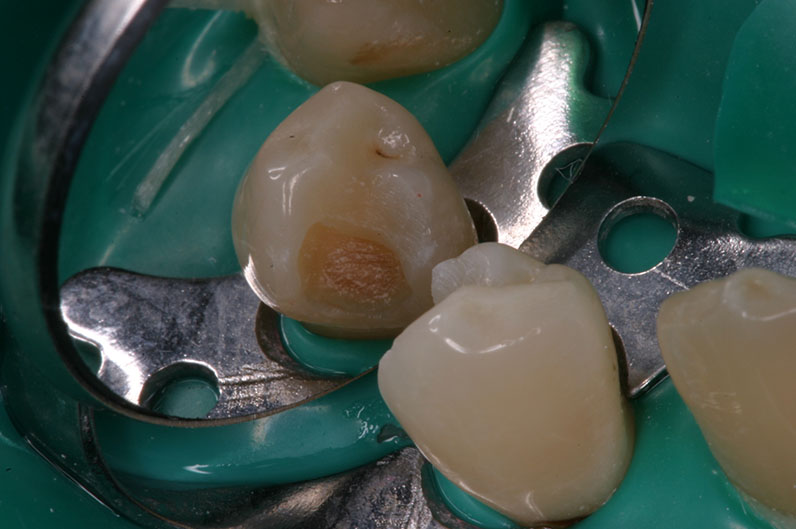

Proface помогает клинически определить наличие бактериально инфицированных твердых тканей зуба, в частности инфицированного дентина. Таким образом, экскавация кариозного поражения является более эффективной по сравнению с традиционно применяемыми методами (зондирование, окрашивание пораженных тканей), которые позволяют лишь косвенно сделать вывод о наличии инфицированного дентина. Световой зонд Proface, используемый вместе с диагностическими очками, представляет собой инструмент для непосредственной визуализации бактериально инфицированного дентина (именуемого в дальнейшем «остаточной кариес») и оценки успешного результата экскавации кариеса.

Принцип действия светового зонда Proface основан на методе FACE (Экскавация кариеса с помощью флуоресценции), эффективность которого была доказана в различных клинических исследованиях.